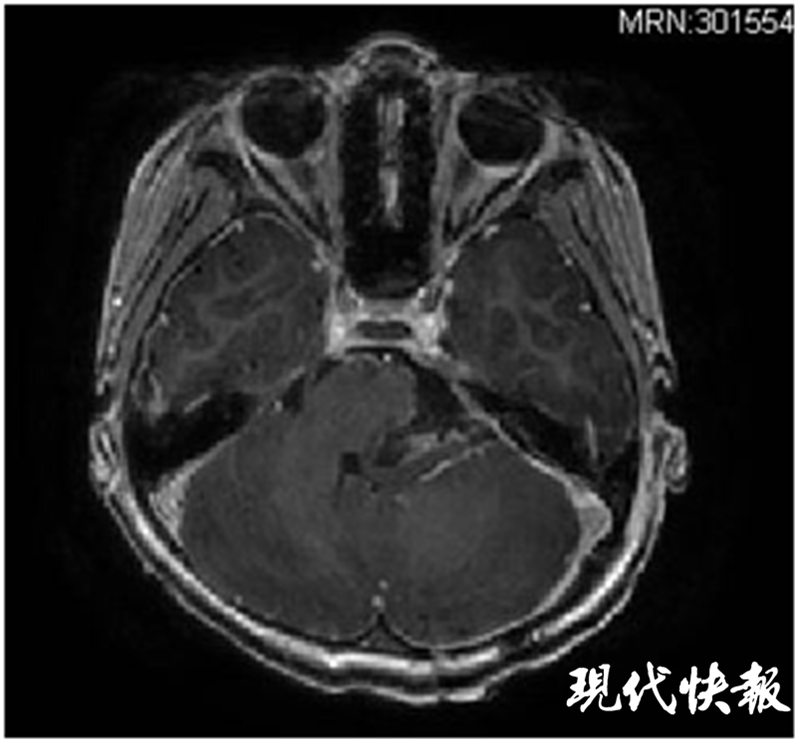

時(shí)間推回到一個(gè)月前,剛滿6歲的諾諾突然直喊頭痛,并伴隨頻繁嘔吐。當(dāng)?shù)蒯t(yī)院首先給諾諾進(jìn)行了消化道的檢查,未見異常。但進(jìn)一步的顱腦核磁共振檢查卻發(fā)現(xiàn)后腦部位長了一個(gè)巨大腫瘤,腦干與小腦已嚴(yán)重受壓變形。

△術(shù)前核磁共振:黃色標(biāo)記為腦干,紅色標(biāo)記為腫瘤